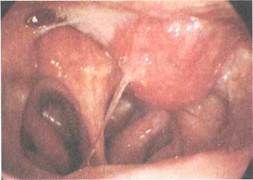

Рис. 7.3. Эндоскопическая картина. Юношеская ангиофиброма.

Юношеская (ювенильная) ангиофиброма. Это опухоль носоглотки, исходящая из ее купола или области крылонебной ямки, по гистологическому строению имеющая доброкачественный характер, однако по клиническому течению (деструирующий рост, сильные кровотечения, частые рецидивы после операции, прорастание в околоносовые пазухи и даже в полость черепа) проявляющая себя как злокачественное образование (рис. 7.3).

При передней и задней риноскопии можно видеть округлую, гладкую или бугристую опухоль ярко-красного цвета, плотную при пальцевом исследовании или при ощупывании зондом. Фиброма обычно заполняет носоглотку и может свисать в средний отдел глотки. При пальпации опухоль может обильно кровоточить, основание ее определяется в верхнем отделе носоглотки.